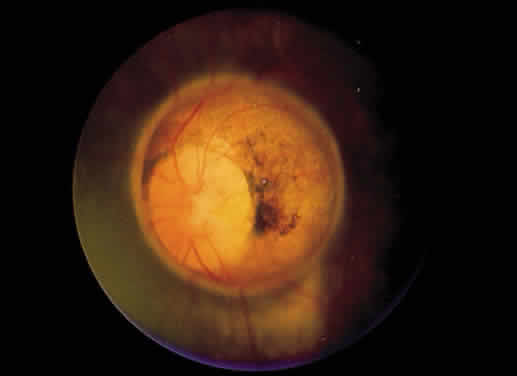

On fluorescein angiography, small arteriovenous communications have been noted in some eyes with macrovessels.31,33 Archer and associates refer to such eyes as having a group I, or mild, arteriovenous communication.33 Patients classified as group II have a more pronounced communication, with large vessels both entering and leaving the optic disc, and in group III the malformation is so pronounced that visual acuity is decreased (Fig. 6). The abnormalities seen in groups II and III usually are referred to as racemose angiomas rather than macrovessels. Patients with anomalies of the character of these latter two groups, in association with vascular malformations of the skull or central nervous system, are considered to have the Wyburn-Mason syndrome.34 However, eyes with congenital retinal macrovessels do not necessarily have arteriovenous communications, and systemic abnormalities have not been associated with these milder vascular abnormalities. Whereas the earlier described arteriovenous anomalies are thought to be congenital, remodeling of some of the more bizarre malformations (group III) has been observed.35

Fig. 6. Right eye of a 20-year-old patient with a large congenital arteriovenous anastomosis, also referred to as a racemose angioma. The visual acuity in this eye was no light perception, and additionally, the patient had an arteriovenous malformation in the jaw, which produced severe bleeding at the time of dental extraction. (Courtesy of Dr. Jerry Shields)